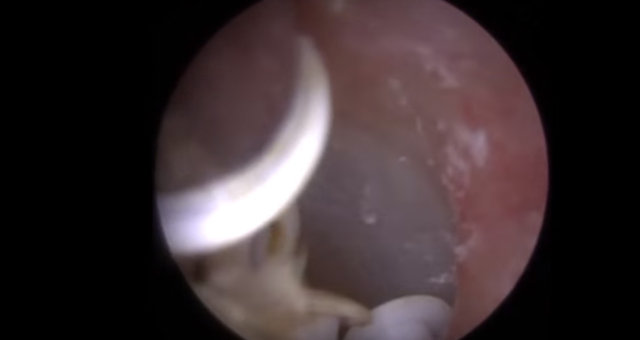

Kulağından 22 tane nesne çıkarılan adam hayrete düşürdü. İşin garip yanı ise kulağının içinden çıkan şeylerin işitme cihazı olmasıydı...